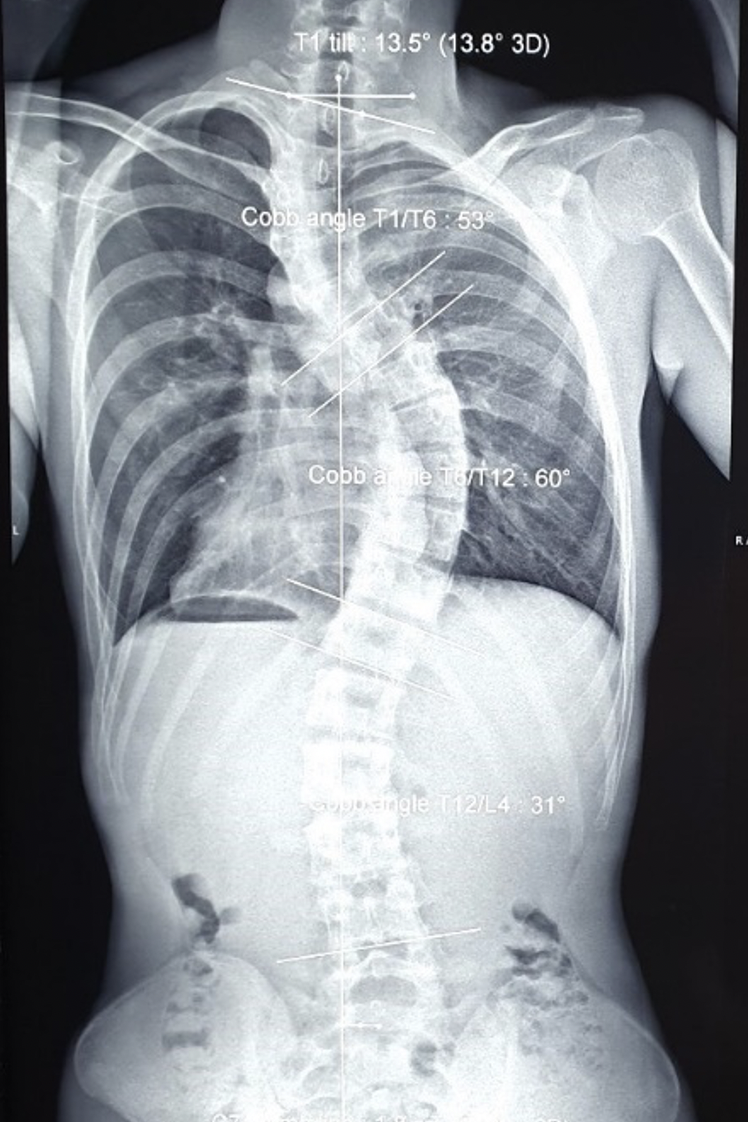

Vai trái Đ. lệch cao gần 5cm so với vai phải, lồng ngực biến dạng và lệch vẹo khung chậu. Ảnh chụp X-quang ghi nhận bệnh nhân bị vẹo cột sống đoạn ngực chữ S rất nặng.